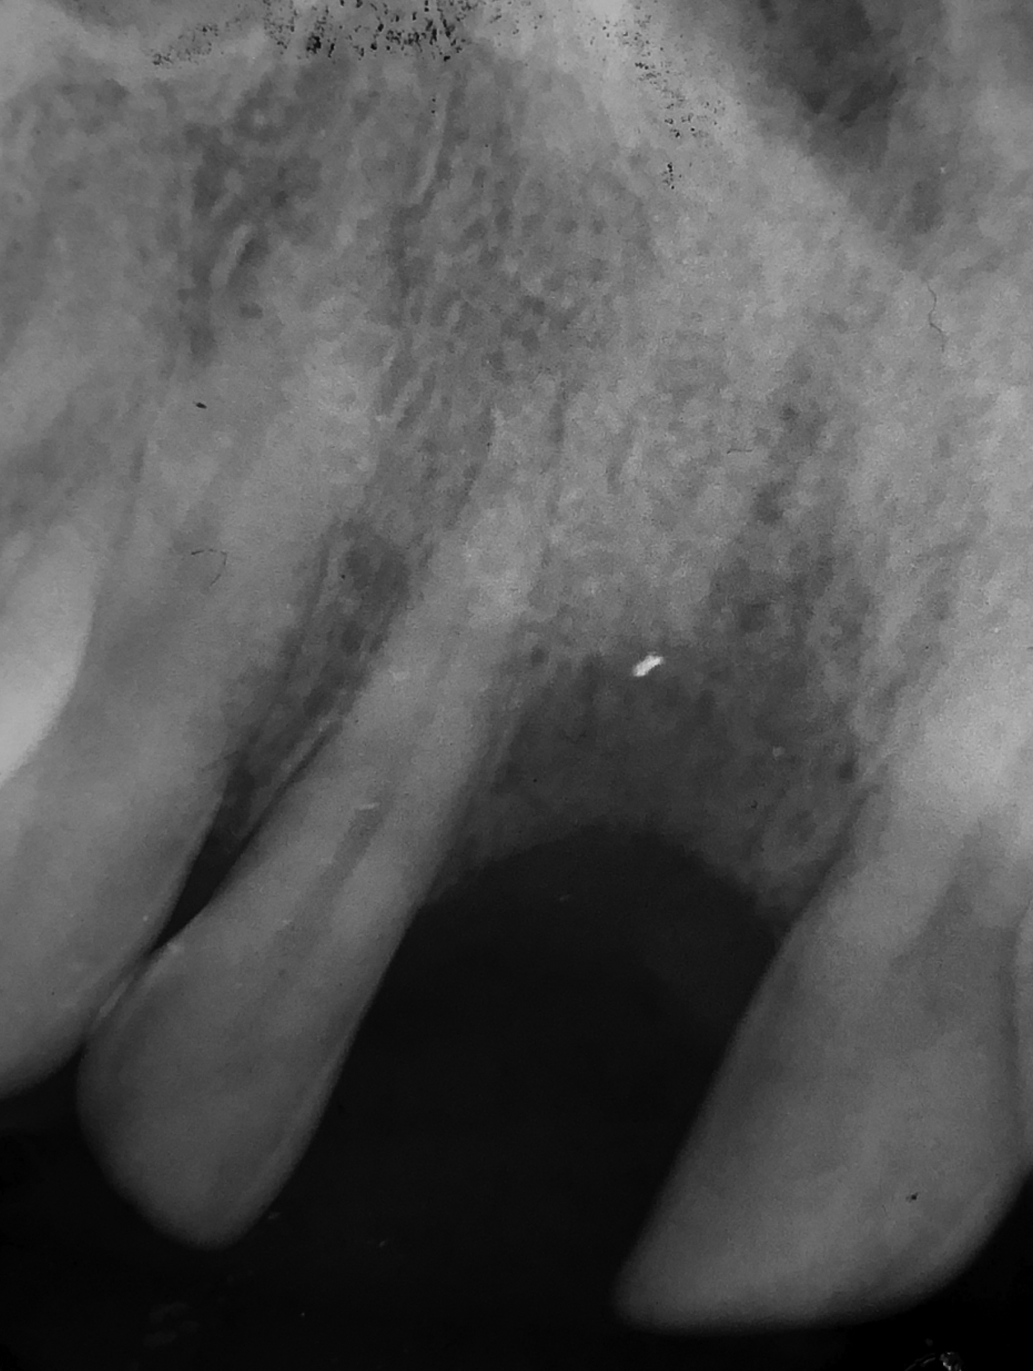

Initial situation after extraction of tooth 11 due to trauma. The patient wishes to replace the missing tooth with an implant. In March 2001, pathological changes were detected in the implant site. A sequestrectomy was performed, and the gap was treated with a removable temporary restoration.